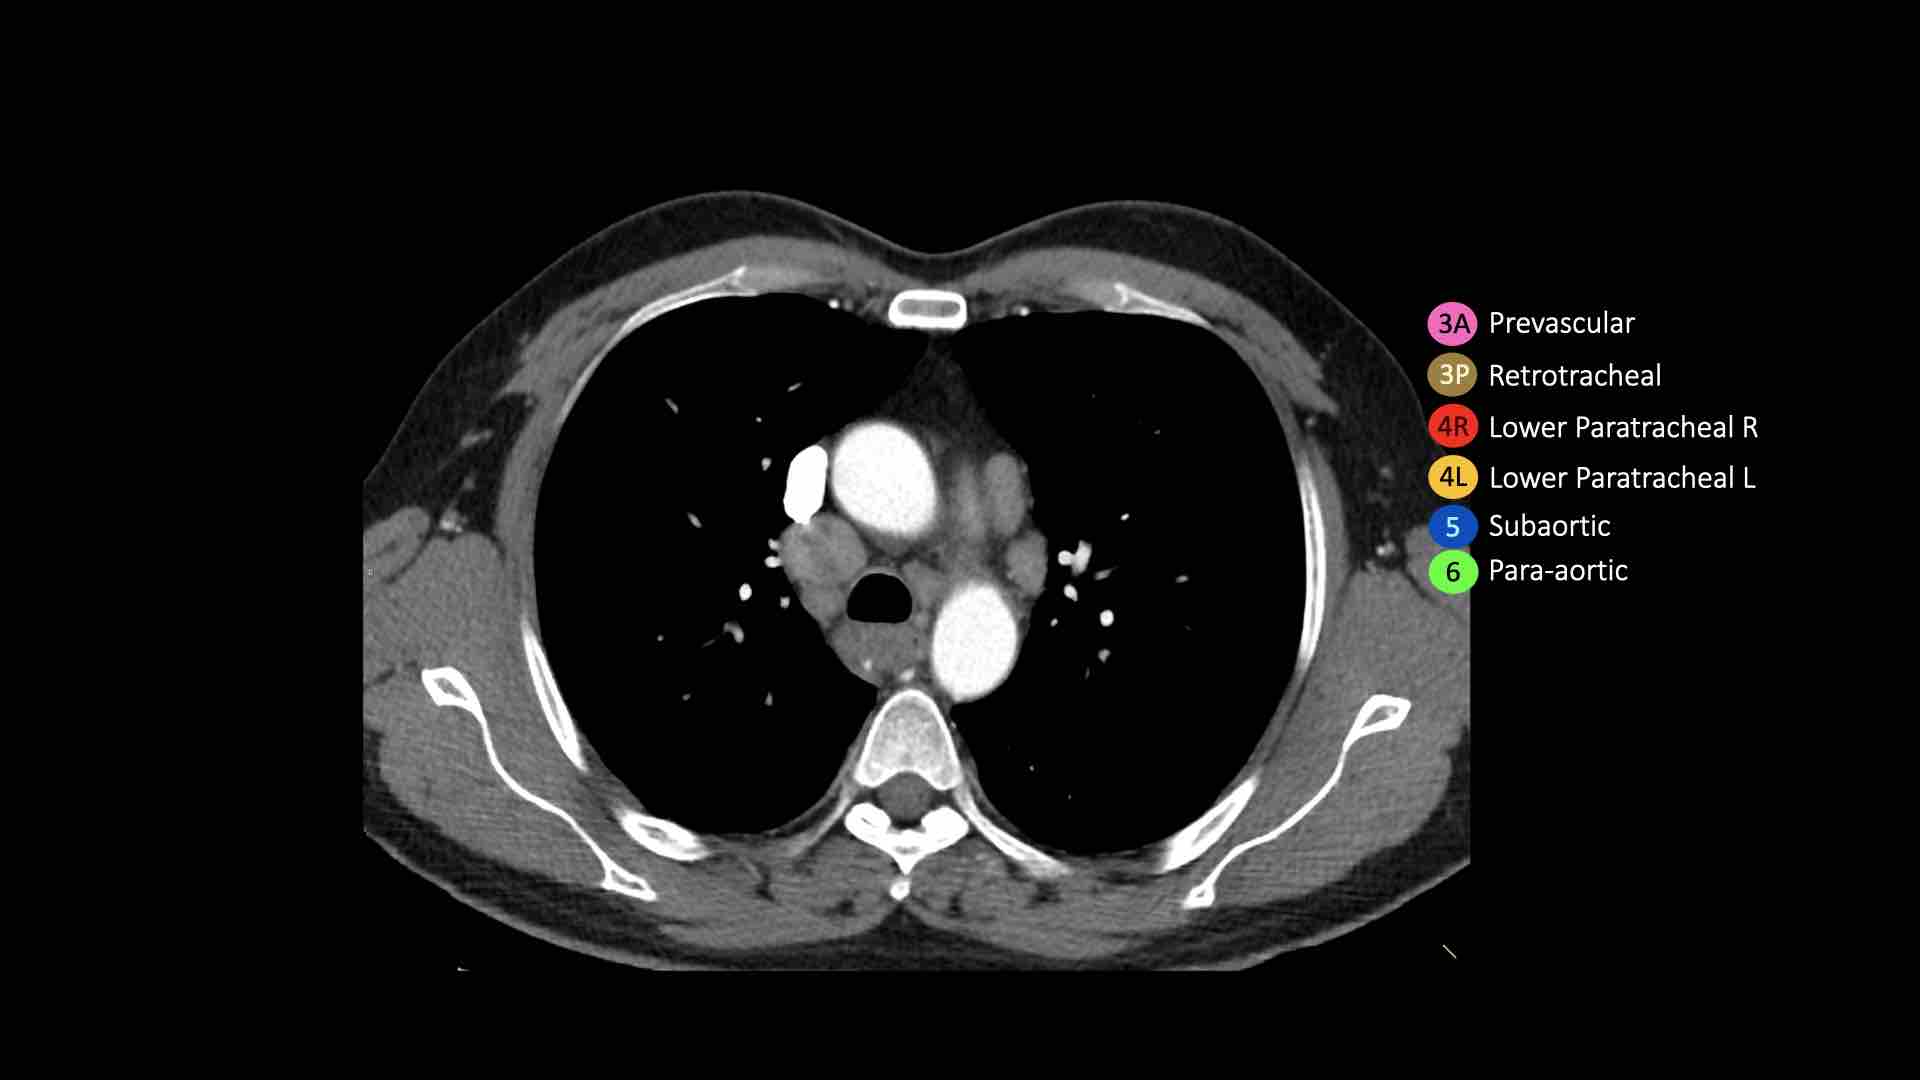

4L. Hạch cạnh khí quản dưới bên trái

Hạch nhóm 4L là các hạch cạnh khí quản dưới nằm bên trái bờ trái của khí quản, giữa đường nằm ngang tiếp tuyến với bờ trên quai động mạch chủ và đường tiếp tuyến với bờ trên động mạch phổi trái.

Nhóm này bao gồm các hạch cạnh khí quản nằm ở phía trong dây chằng động mạch.

Hạch nhóm 5 (cửa sổ phế động mạch) nằm ở phía ngoài dây chằng động mạch.

Bên trái là hình ảnh ngay trên mức thân động mạch phổi, cho thấy các hạch cạnh khí quản dưới bên trái và bên phải.

Ngoài ra còn có các hạch nhóm 3 và nhóm 5.

Bên trái là hình ảnh ở mức phần dưới khí quản, ngay trên carina.

Bên trái khí quản là các hạch 4L.

Lưu ý rằng các hạch 4L này nằm giữa thân động mạch phổi và động mạch chủ, nhưng không nằm trong cửa sổ phế động mạch, vì chúng nằm ở phía trong dây chằng động mạch.

Hạch nằm bên ngoài thân động mạch phổi là hạch nhóm 5.

5. Hạch dưới động mạch chủ

Hạch dưới động mạch chủ hay hạch cửa sổ phế động mạch nằm ở phía ngoài dây chằng động mạch hoặc động mạch chủ hoặc động mạch phổi trái, ở đoạn gần trước nhánh đầu tiên của động mạch phổi trái, và nằm trong bao màng phổi trung thất.

6. Hạch cạnh động mạch chủ

Hạch cạnh động mạch chủ (động mạch chủ lên hoặc cơ hoành) nằm ở phía trước và bên ngoài động mạch chủ lên và quai động mạch chủ, từ bờ trên đến bờ dưới của quai động mạch chủ.